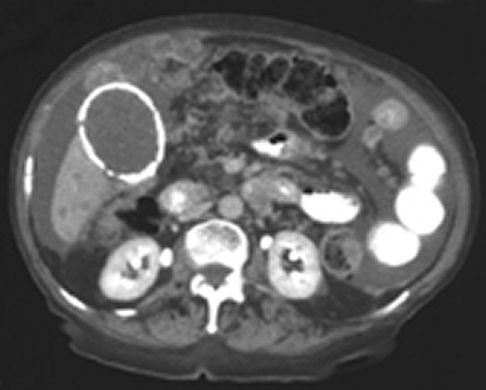

A computed tomographic scan showed that the calcification seen on the plain abdominal radiograph represented the wall of

the gallbladder (image below). The scan also showed ascites, multiple lesions in the liver, and nodularity of the

peritoneum and small bowel mesentery. These findings suggested metastatic carcinoma of the gallbladder, but the patient

refused further investigation.